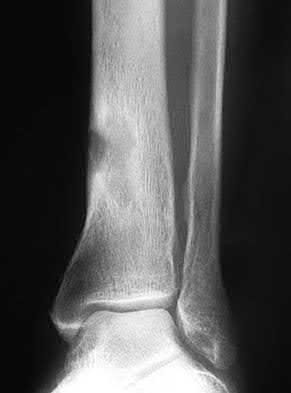

A 25-year-old female is involved in a motor vehicle collision. She presents with the isolated injury seen in Figures A through D. Her leg is swollen but her skin is intact. She has no clinical signs of compartment syndrome. Which of the following treatment options will allow for maintenance of fracture alignment and minimize the risk of soft tissue complications?

The patient presents with a closed distal third metaphyseal-diaphyseal distal tibia fracture with simple intra-articular extension. Immediate intramedullary nailing along with percutaneous fixation of the articular component provides appropriate restoration of length, rotation and alignment and minimizes the risk of wound complication.

Displaced distal third tibia fractures may be associated with simple intraarticular extension. Operative treatment of intra-articular distal tibia fractures has historically been performed with open reduction and internal fixation. Early open reduction and plate fixation of pilon fractures has been associated with high rates of infection and wound complication. In select patterns with simple articular extension, percutaneous screw fixation and medullary nailing may provide appropriate reduction with minimal soft-tissue risk.

Figures A and B demonstrate a distal third tibial shaft fracture with simple intra-articular extension. The axial and coronal CT cuts in Figures C and D further clarify the articular injury. Illustrations A and B demonstrate a comminuted distal third tibial fracture with simple intra-articular extension. Illustrations C and D are fluoroscopic images of the same injury after intramedullary nailing and percutaneous fixation of the articular component.